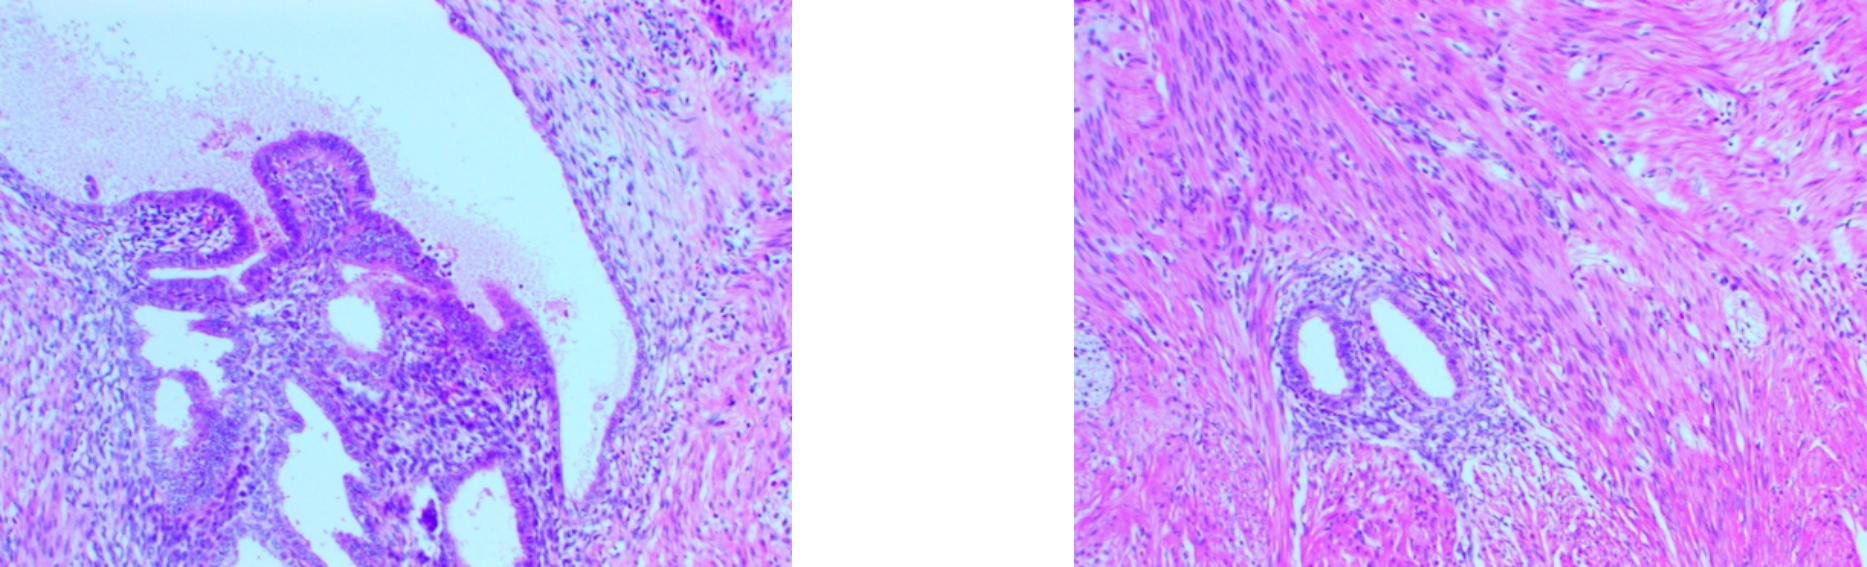

摘要:背景与目的 结肠横纹肌样癌(RCC)是一种极为罕见且高度侵袭性的肿瘤,常伴广泛转移,预后极差,目前尚无标准化治疗方案。本研究报告1例RCC,并结合既往文献总结其临床、病理及分子特征,以期提高对该病的认识。方法 回顾性分析中南大学湘雅医院收治的1例RCC的临床表现、影像学、病理及免疫组化特征,同时检索并整理国内外已报道的36例RCC,汇总其临床资料、免疫表型、基因变异、治疗方式及随访结果。结果 患者为71岁男性,表现为腹胀、腹痛及排便改变,影像及内镜提示升结肠肿瘤并不完全性梗阻。行腹腔镜右半结肠癌根治术,病理示低分化RCC,侵透浆膜层,淋巴结转移4/21;免疫组化示角蛋白AE1/AE3(+)、vimentin(+)、CDX2(-)、CK20(-),Ki-67(80%+),INI1表达保留;基因检测显示KRAS突变、BRAFV600E野生型。患者因经济原因未行放化疗,术后3个月出现腹膜转移而死亡。纳入的37例患者,男女比1.3∶1,平均年龄66岁,62%病变位于右半结肠;多数表现为低分化、横纹肌样细胞占主导,97.06%表达vimentin,100.00%表达角蛋白AE1/AE3,约85.71% CDX2(-);基因中65.00%伴BRAFV600E突变,约22.73%存在KRAS突变;MMR状态中pMMR占60.71%,dMMR占39.29%。多数患者行手术治疗,但78.79%在术后1年内死亡,中位生存6.0个月,仅少部分接受辅助化疗或免疫治疗者生存超过1年。结论 RCC具有高度恶性、生长迅速、易发生早期转移及复发的特点,对常规化疗反应差。其发生可能与肿瘤去分化、INI1缺失及BRAF/KRAS通路异常激活相关。手术仍为主要治疗方式,但术后应积极评估免疫治疗、生物制剂和放疗等综合策略的潜在价值。需进一步研究其分子机制及有效治疗手段。